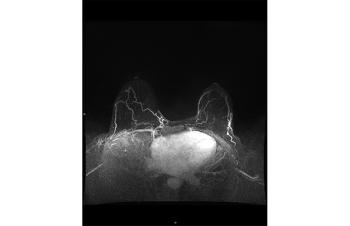

In observational studies, adding contrast-enhanced MRI to annual mammography in BRCA mutation carriers significantly improved detection of early, treatable breast cancers with a combined sensitivity of 94% compared to 39% with mammography alone.18,22,23 MRI provides a functional assessment of breast tissue. Contrast- enhanced MRI can detect microvascular changes and peritumoral inflammation as the contrast accumulates rapidly, and is then washed out rapidly, in more vascular tumors compared to benign breast tissue. Consequently, annual contrast-based MRI has been incorporated into breast cancer surveillance guidelines for women at the highest risk of breast cancer.24